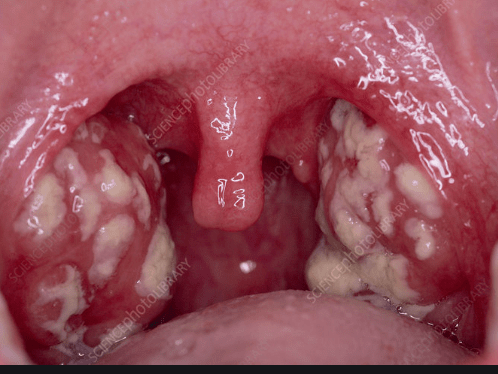

Tonsils are oval-shaped organs placed in the folds on both sides of the back of the throat. The Latin term “tonsillitis”, which means infection of the tonsils, is widely used both in medical language and in daily speech.

– Red and swollen tonsils

– Yellow-white plaques on the tonsils